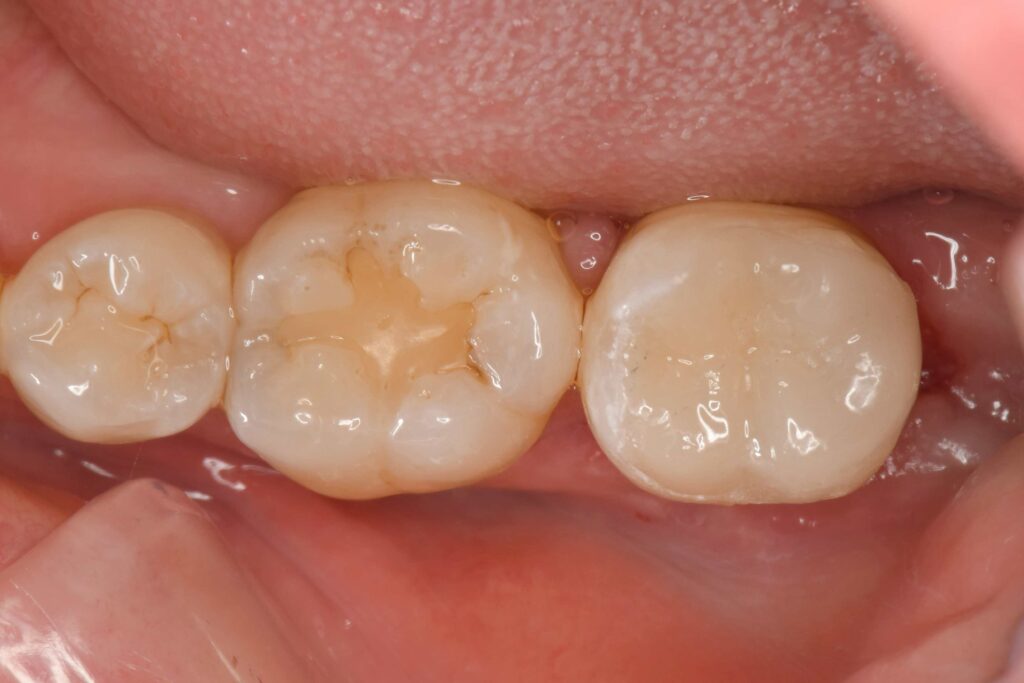

2週間後に届いたオーバーレイ(テーブルトップベニヤ)の完成品です。

再びラーバーダム防湿を行い、清潔な環境を確保していきます。

磨き残しがないかプラークチェッカーで赤く染めていきます。